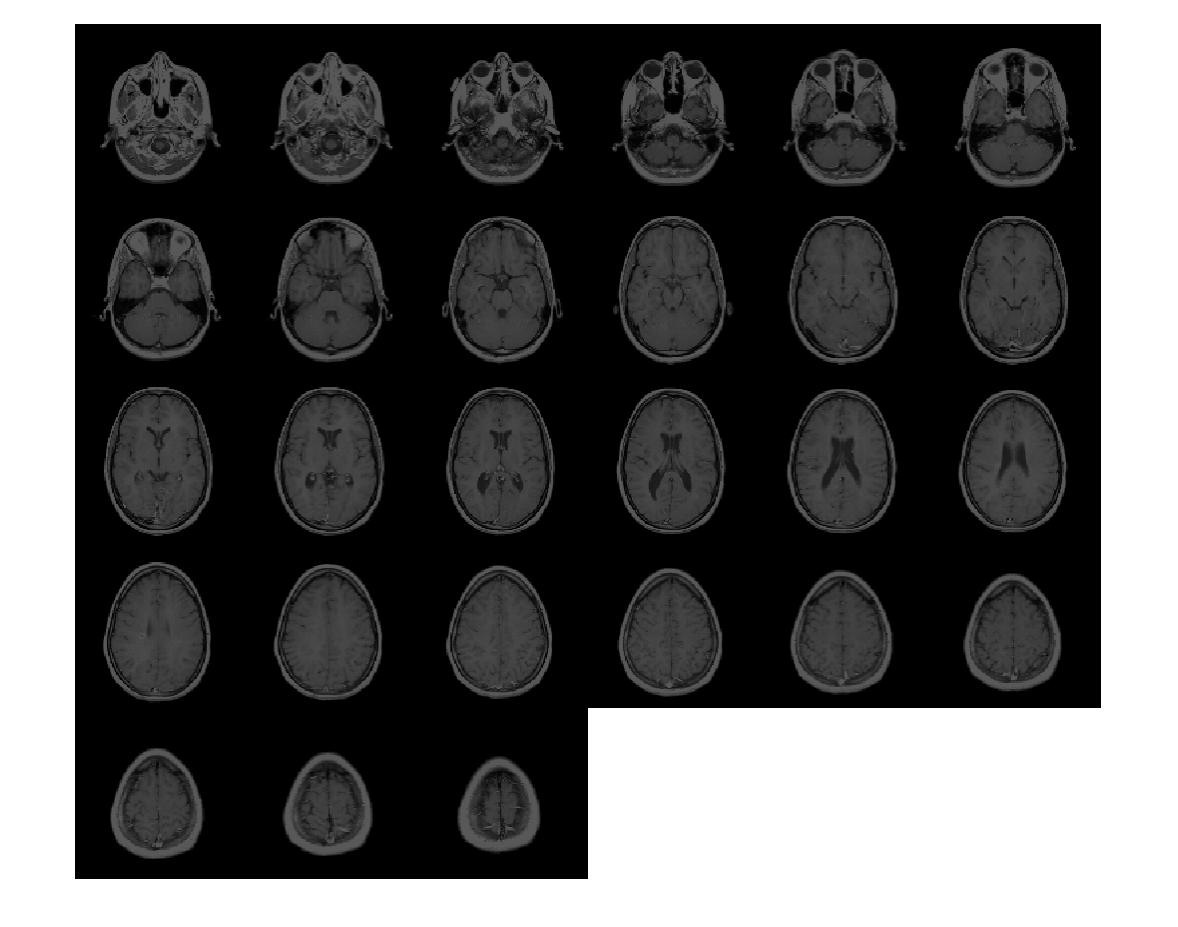

Загрузите объем MRI. Этот объем хранится как 4-D массив с одноэлементной размерностью. Создайте 3-D полутоновый объем при помощи squeeze функция, чтобы удалить одноэлементную размерность.

load mri;

V = squeeze(D);

Отобразите плоскости объема.

montage(D,'BackgroundColor','w')

Figure contains an axes object. The axes object contains an object of type image.